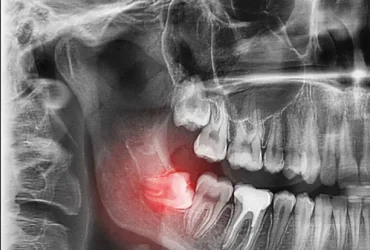

ฟันคุดคือ ฟันกรามซี่ในสุด ทั้งหมด 4 ซี่ บน ล่าง ซ้าย ขวา ไม่สามารถขึ้นได้ตามปกติเพราะพื้นที่ไม่เพียงพอให้ฟันสามารถขึ้นมาได้ บางซี่อาจจะโผล่ขึ้นมาเล็กน้อย และบางซี่ถูกฝั่งอยู่ในกระดูดขากรรไกร อาจจะขึ้นตรง เอียงหรือนอนในแนวราบส่วนใหญ่ฟันคุดมักพบว่าอยู่ที่ฟันกรามซี่ล่างในสุดและพบมากสุดในช่วงอายุ ประมาณ 16 – 25 ปี หรืออาจจะช้ากว่านั้น